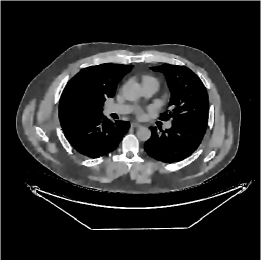

III-B3 Generalization Capability Comparisons between a “Denoising” Deep NN and the Proposed PWLS-ST- Method

This section compares the generalization capabilities between the proposed MBIR method, PWLS-ST-, and a denoising deep NN, FBPConvNet [14], that are trained from the phantom data; in particular, we tested the trained PWLS-ST- and FBPConvNet models to phantom and clinical scan data. The results in Fig. 6 show that the non-MBIR FBPConvNet method has higher overfitting risks, compared to the proposed PWLS-ST- MBIR method. When tested on clinical scan data, PWLS-ST- achieves much more accurate reconstruction, compared to FBPConvNet. See Fig. 6(b). When tested on phantom data, FBPConvNet generates more unnatural features as the number of views reduces, although it gives lower RMSE values compared to PWLS-ST-. See zoom-ins in Fig. 6(a). The FBPConvNet results above correspond to those in the recent work [16] that FBPConvNet [14] generated some unexpected structures.